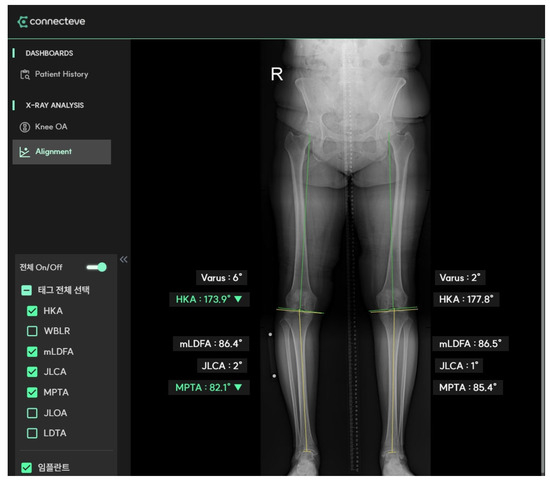

| HKA (°) | 9.94 ± 3.32 (3.7~17.6) | AI |

| mLDFA (°) | 89.03 ± 2.23 (83.7~97.9) | AI |

| JLCA (°) | 4.64 ± 2.93 (−3.4~12.6) | AI |

| MPTA (°) | 82.49 ± 2.07 (75.8~88.4) | AI |

| Leg length (mm) | 715.18 ± 46.05 (611.1~838.17) | Human |

| Length, tibia (mm) | 309.91 ± 30.15 (103.8~378.2) | Human |

| Width, proximal tibia (mm) | 72.88 ± 5.11 (64.58~86.38) | Human |

| WBL position (%) | 7.4 ± 13.3 (−29.4~31.2) | Human |